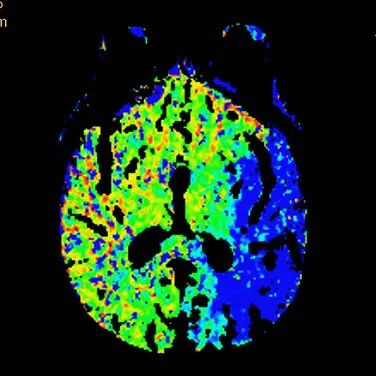

查体BP 160/89mmHg,清醒,双眼左侧凝视位、不可纠正,混合性失语,右侧中枢性面舌瘫,右侧肢体肌力0级,右侧病理征阳性。NIHSS评分18分。随机血糖4.8mmol/L。心电图:正常。颅脑CT无出血及新发梗死灶,多模态CT示左侧大脑中动脉闭塞、左侧大脑半球低灌注。

多模态CT。